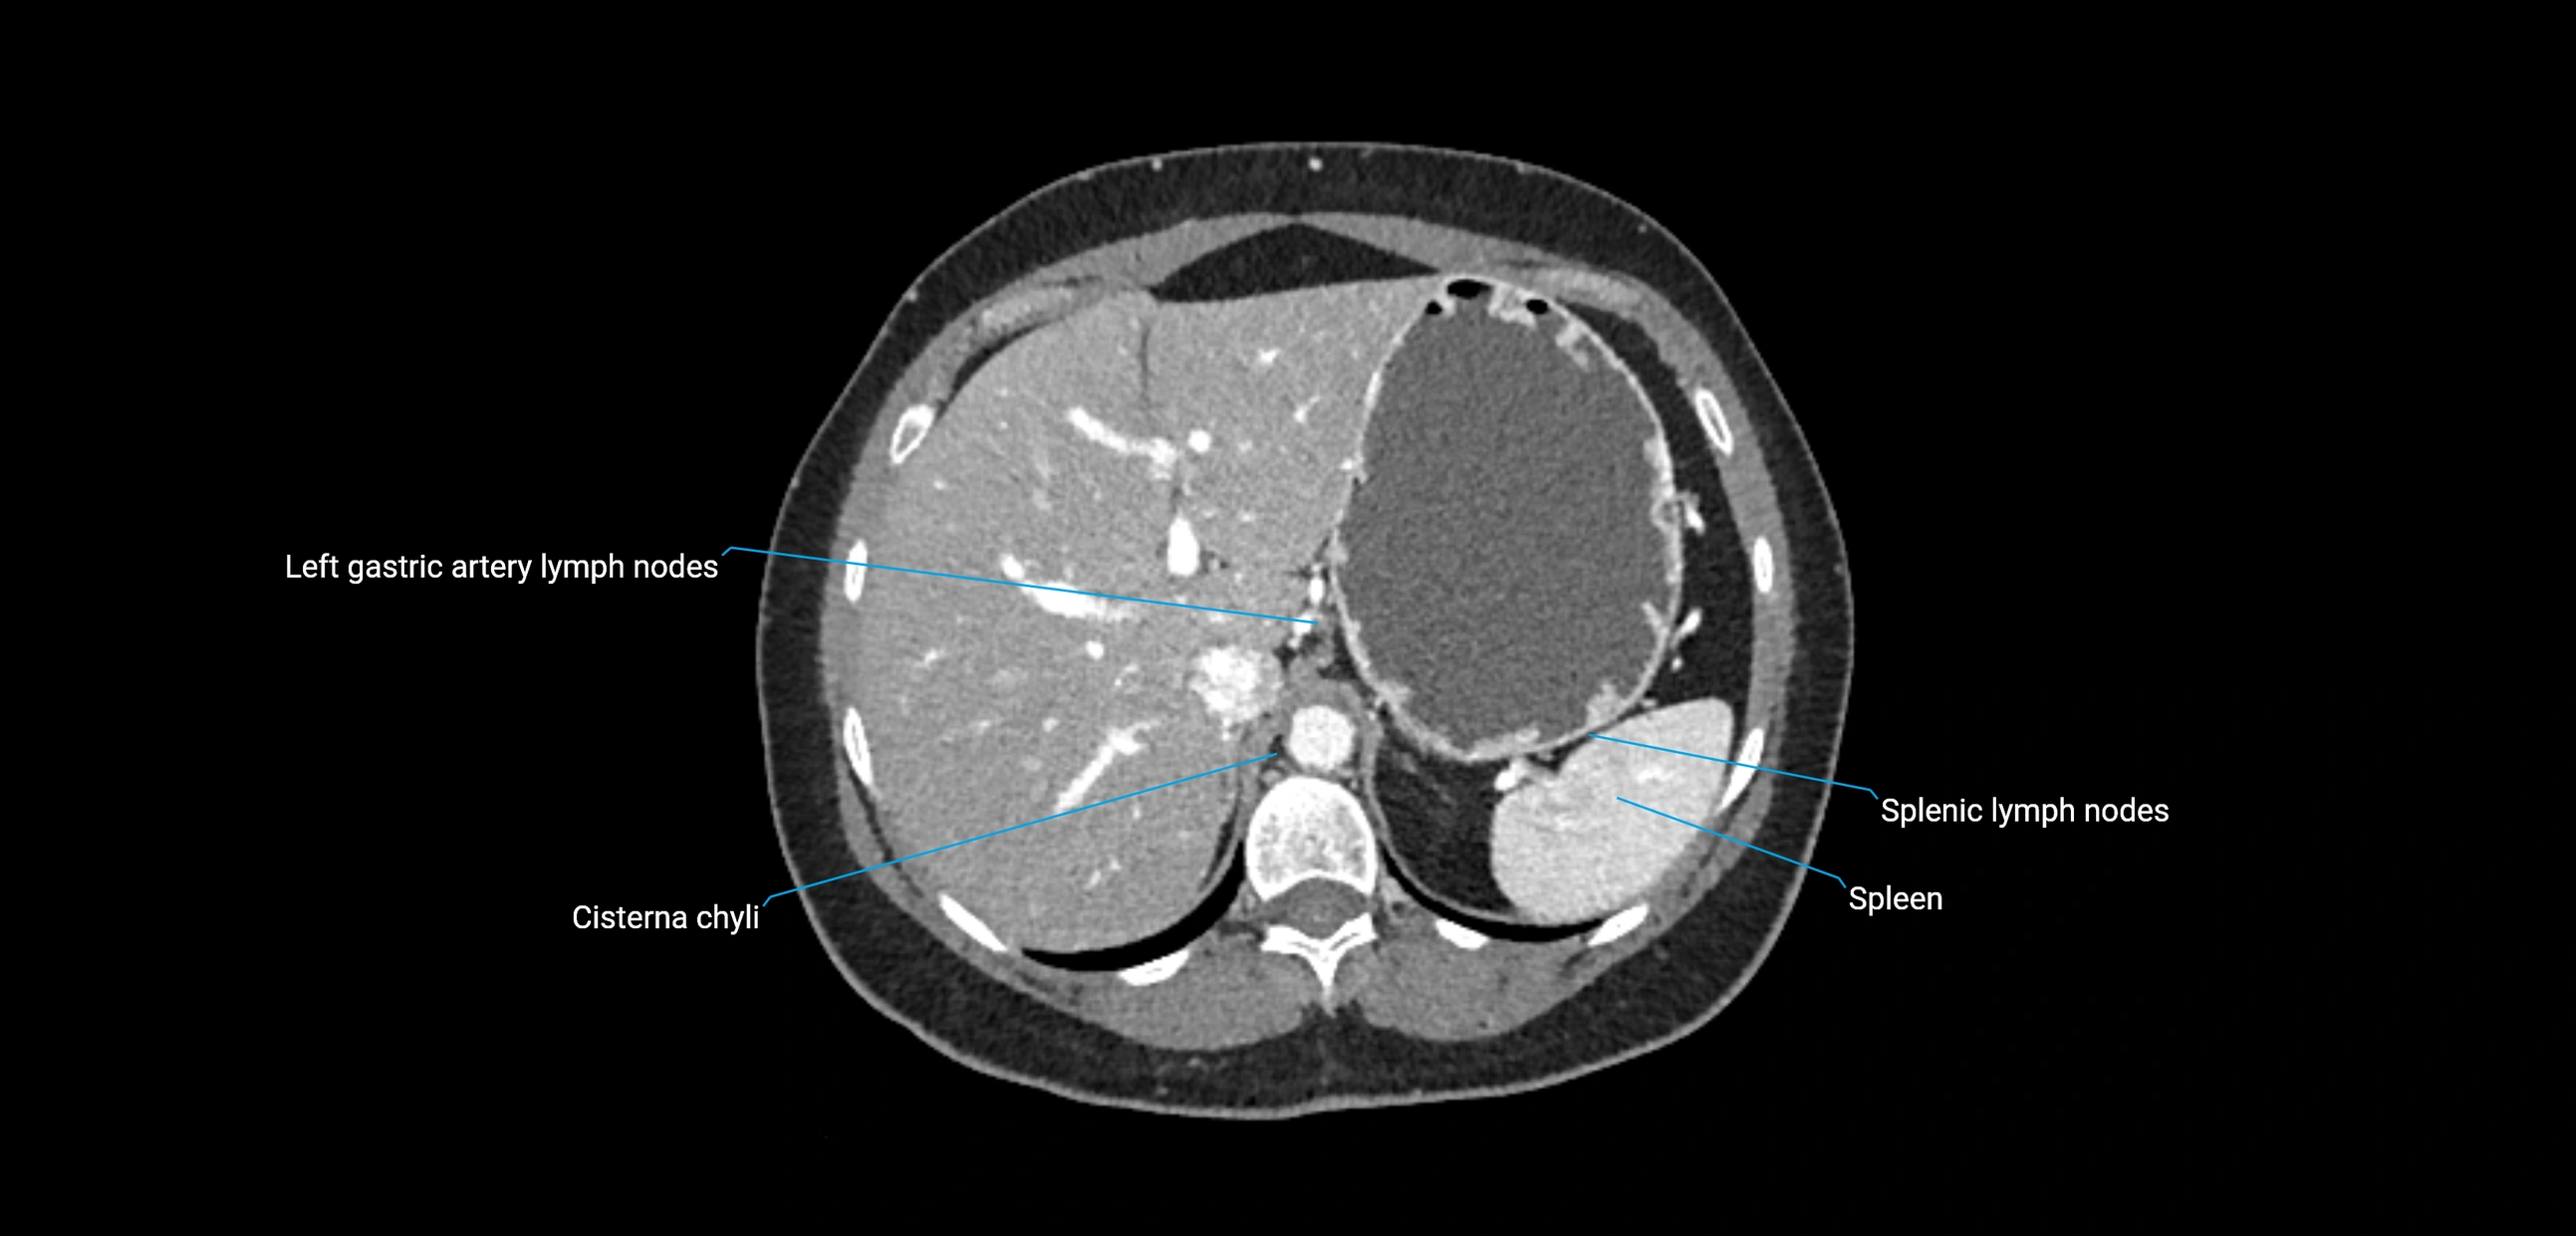

CT image

image